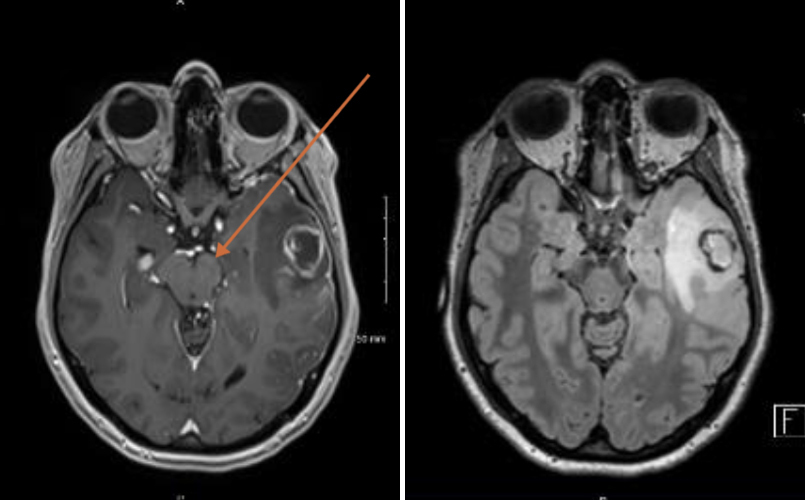

Votre externe vous montre l’imagerie cérébrale du patient (figures 2 et 3) : Figures 2 et 3 (Source : Salomé Oranger, La Revue du Praticien)

Question 5 - Concernant les imageries cérébrales précédentes (une ou plusieurs réponses possibles) :

Imagerie par résonance magnétique (IRM) en séquence T1 injecté.

Séquence FLAIR : liquide céphalorachidien (LCR) en hyposignal, substance grise en blanc.

Finalement vous comprenez que votre externe s’est trompé de patient car il s’agit d’une IRM cérébrale en séquence FLAIR montrant un abcès cérébral en lobe temporal gauche et non l’imagerie de votre suspicion initiale, celle d’une méningo-encéphalite herpétique. Les résultats sanguins montrent : hémoglobine (Hb) = 14 g/dL ; globules blancs (GB) = 5 G/L dont 2 G/L de polynucléaires neutrophiles (PNN) et lymphocytes 3 G/L ; protéine C réactive (CRP) = 60 mg/L ; bilan hépatique normal. La biologie du LCR retrouve : protéinorachie = 1,1 g/L ; hématies = 10/mm3 ; leucocytes = 240/mm3. Examen direct négatif. PCR HSV en cours.